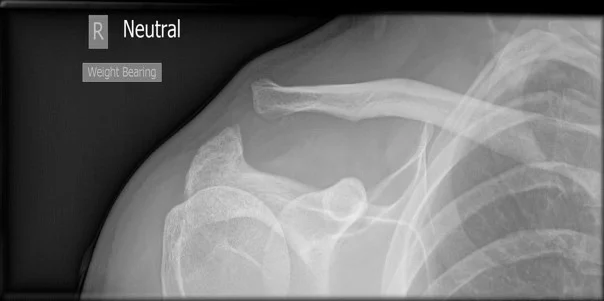

A 19 year-old male presents to the emergency department with a complaint of right shoulder pain. He was tackled from behind in a rugby game three days prior to presentation and has been experiencing pain over the anterior aspect of his right shoulder since that time. Physical exam is notable for tenderness over the right acromioclavicular (AC) joint and pain with both active and passive range of motion of the right shoulder. X-rays (Figure 1) show “no obvious fracture or subluxation.” However, based on your exam and clinical suspicion, closer inspection reveals abnormal alignment between the clavicle and the acromion consistent with AC joint injury.

Figure 1

Figure 1: Case courtesy of Dr Henry Knipe, <a href="https://radiopaedia.org/">Radiopaedia.org</a>. From the case <a href="https://radiopaedia.org/cases/30774">rID: 30774</a>